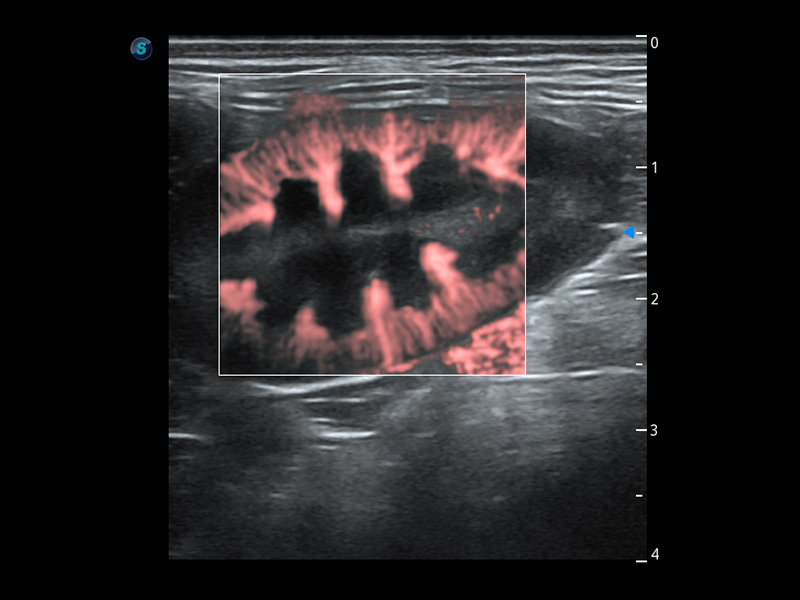

ProPet 60 作为一款高端台式动物超声设备,为动物医生的日常诊断提供了一系列贴合动物临床需求、解决临床实际问题的高级成像功能。凭借全系列高清探头,满足医生对腹部、心脏、生殖、浅表、肌骨等成像的所有需求,切实帮助您提升检查效率,提高诊断信心。

动物是人类最亲密的朋友和最值得信赖的伙伴。DB中国旗舰官方网站也一直致力于探索动物专用的超声影像解决方案。 全新推出的ProPet系列,是DB中国旗舰官方网站在动物超声影像智能化、专业化、精准化的一次跨越式革新。动物不能用言语来表述自己的不适,通过超声影像,ProPet系列搭建了动物医生与不同物种沟通的“桥梁”,为动物医生注入了“治愈之力”。